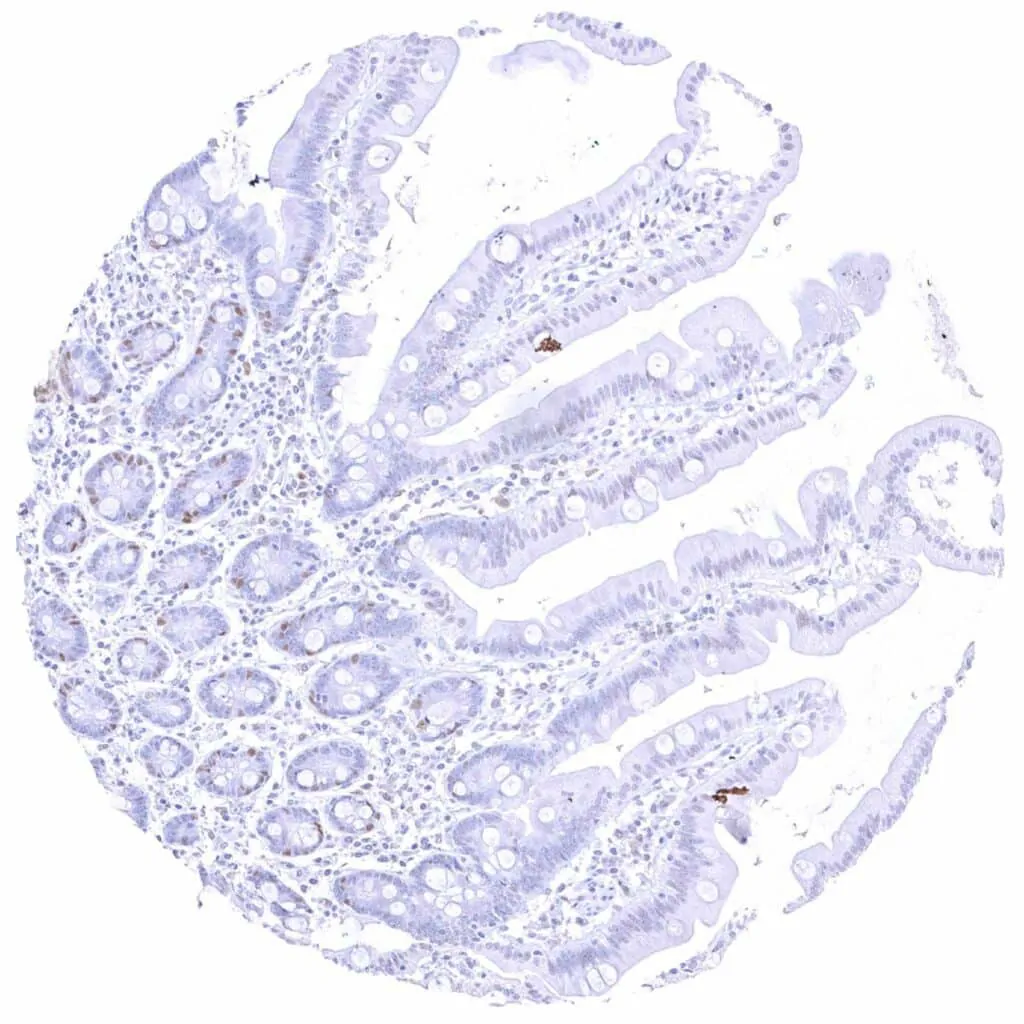

Appendix, mucosa – Weak to moderate Cyclin E1 staining of a subset of crypt cells